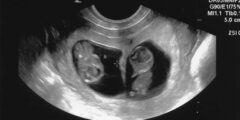

ماذا يعني ظهور خط خفيف في اختبار الحمل بعد ساعات، اختبار الحمل المنزلي هو عبارة عن جهاز بحجم صغير يستخدم للكشف عن هرمون hCG الذي يدل على الحمل، فجسم المرأة يفرز هذا الهرمون في حالة حدوث الحمل، ويتوفر هذا الاختبار في الصيدليات بأنواع وماركات مختلفة، ويتم عمل الاختبار في المنزل بعد تأخر الدورة عن موعدها الطبيعي بأسبوع، وهناك العديد من التساؤلات عنه منها ماذا يعني ظهور خط خفيف في اختبار الحمل بعد ساعات وهذا ما سنتعرف عليه في موقعنا اراء.

شرح نتائج اختبار الحمل المنزلي ببساطة أنه عند ظهور خطين يعني ذلك حدوث حمل، وعند ظهور خط واحد فلا يستدل على وجود حمل، أما نتائج فحص هرمون الحمل hCG فهي كما يلي: